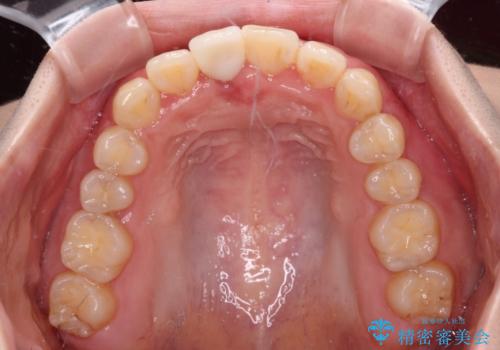

- 矯正装置

- クリアブラケット

- 中学生の頃にぶつけた前歯に不格好なクラウンが装着されており、出っ歯な印象になっていることを気にして来院された患者様です。

ぶつけてしまった歯は保存が困難な状況であったので抜歯をし、ワイヤー矯正により歯列を整えつつ前歯の突出感を解消することとしました。

矯正治療後にはインプラント補綴治療を行うこととしました。